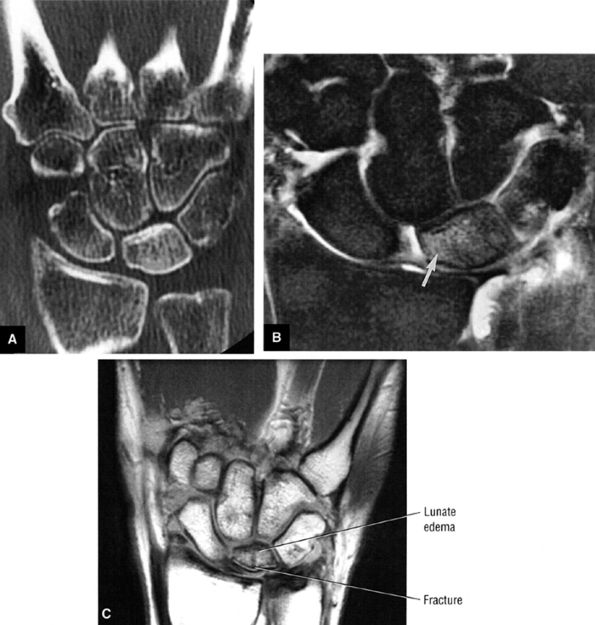

-

Pain and numbness or tingling in the median nerve distribution with increased nocturnal pain and/or burning (can be classified as mild, moderate, or severe based on electrodiagnostic data or by severity of clinical symptoms)

Involvement of the thumb, index, middle fingers, and radial half of the ring finger is most common.

Sensory findings ranging from minimal hypesthesia to complete anesthesia

Muscle atrophy and loss of function are usually late findings, although abductor pollicis brevis involvement and opponens weakness may be seen earlier (opponens atrophy is a late finding).

Positive clinical tests for nerve entrapment: